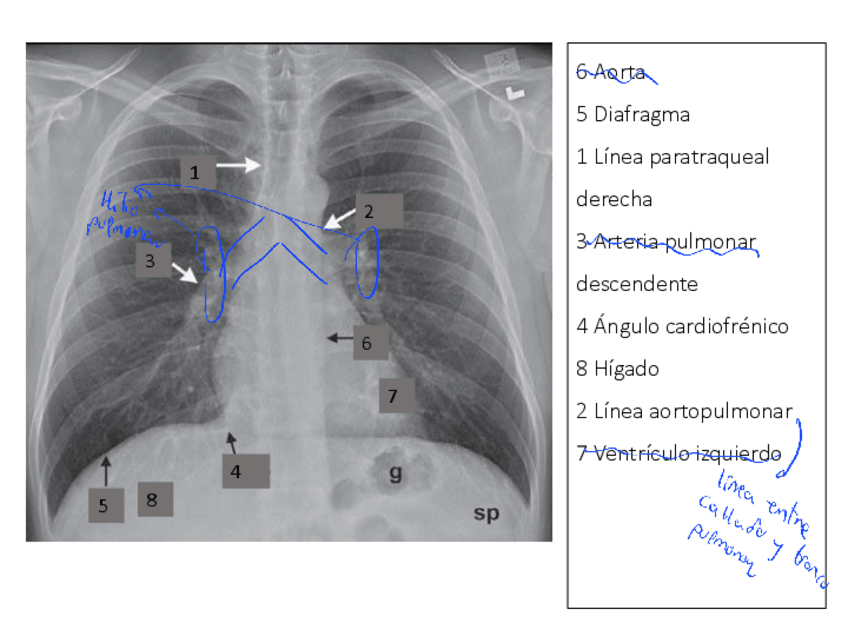

He publicado nuevos apuntes de Anatomía por la imagen: Imagenes-torax-Ap-RespiratorioTODAS-TECNICAS.pdf

27 páginas

He publicado nuevos apuntes de Anatomía por la imagen: Aparato-RESPIRATORIO.pdf

11 páginas

He publicado nuevos apuntes de Anatomía por la imagen: TEMA-5-cardiocirculatorio.pdf

8 páginas